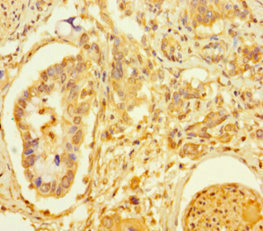

Immunohistochemistry of paraffin-embedded human pancreatic cancer using CSB-PA023302HA01HU at dilution of 1:100